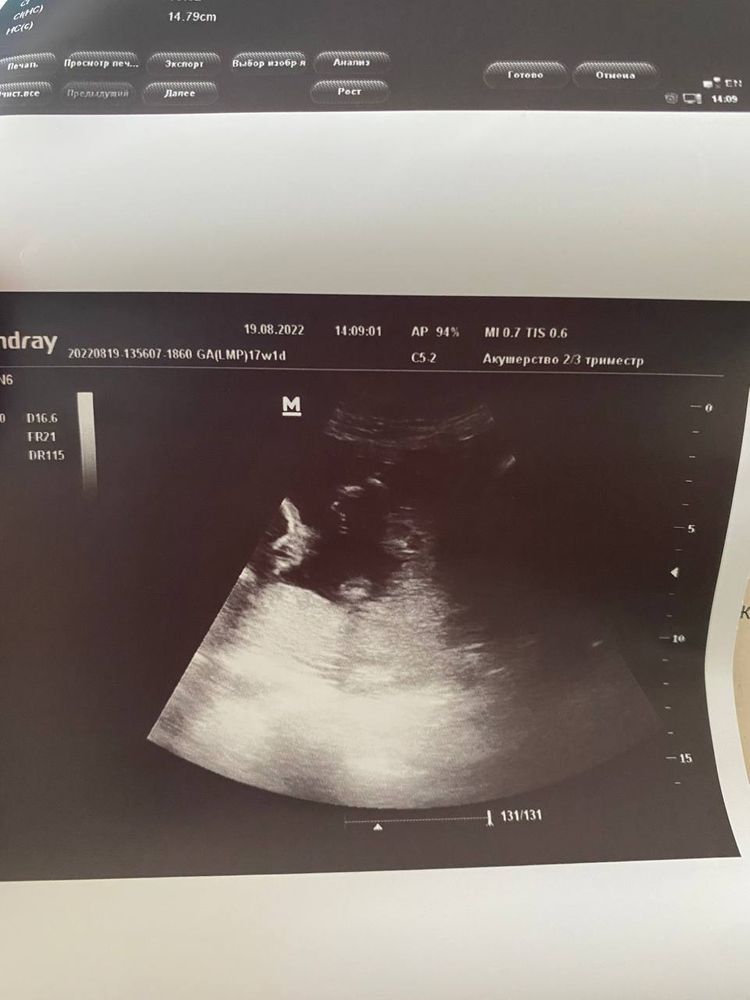

Всем привет! На сроке 17 недель узист сказала, что скорее всего мальчик, фото прилагаю. Но потом показала еще одному врачу фото - сказала, что может быть и девочка и надо посмотреть через пару недель. Вот смотрю и думаю: вроде парень, но столько в интернете похожих фото, где определяли девочку. могли ли ошибиться? Наверное, самая популярная тема тут:)))

Не самое удачное фото, но, по-моему, чисто мальчуковая мошонка) у девочек там такого богатства нет😁

Вроде, я разобралась в Вашем фото))) Всё равно не чёткое. Вроде как, мошонка в кадре, но продольная полоса смущает: то ли блик, то ли половые губы. 🥒 не вижу. Хотя у моего он Задирался часто кверху, но врачи разные, все говорили, что парень 100%.

Алина, не, мальчик у Вас)) Уж оч выделяется))) Писюн - всё же не самое главное на фотках, мошонка всегда больше выделяется